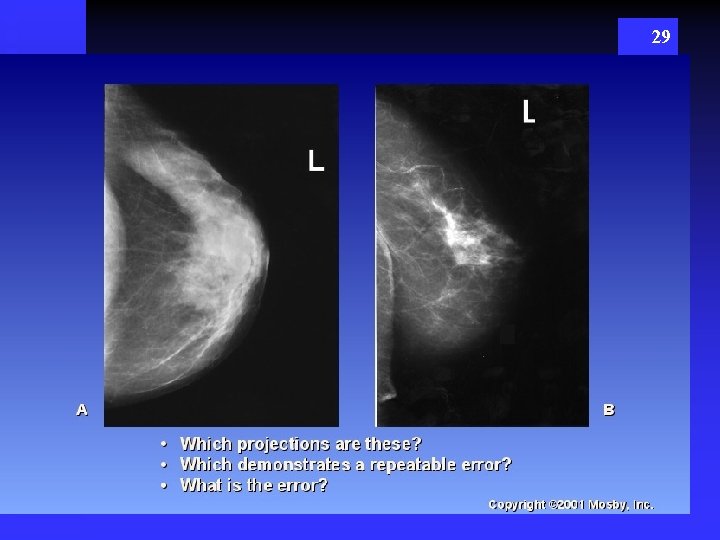

29